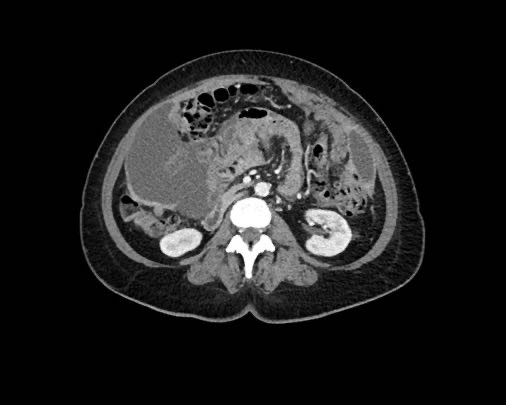

Mạc nối bánh

Mạc nối là một trong những cấu trúc trong ổ bụng đầu tiên bị xâm lấn bởi ung thư phúc mạc.

Hình ảnh gọi là “mạc nối bánh” (omental cake) là kết quả của các nốt khối u lan rộng trong mạc nối lớn.

Tổn thương này có hình ảnh rất điển hình trên cả siêu âm và CT.

Hình ảnh

Hình ảnh CT của mạc nối bánh nổi trong dịch cổ trướng (mũi tên).

Mạc nối nằm ở bụng trái, trải dài từ bờ ngoài dạ dày xuống phía dưới.

Hình ảnh cho thấy cấu trúc dạng nốt không đồng nhất rõ rệt, điển hình của mạc nối bánh.

Các chấm trắng trong mạc nối có thể là các mạch máu.